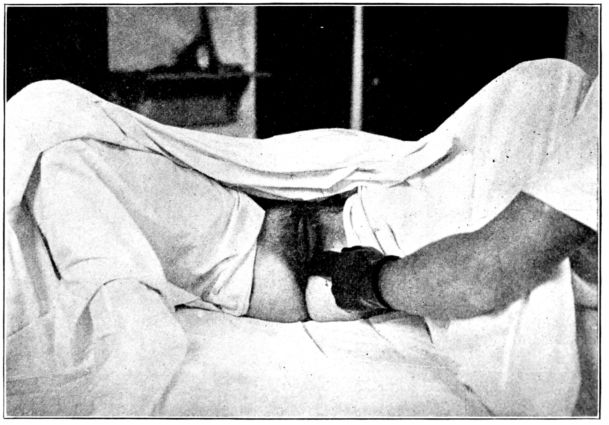

| 74. | Preparing patient for vaginal examination or delivery | 250 |

| 75. | Patient draped for vaginal examination | 251 |